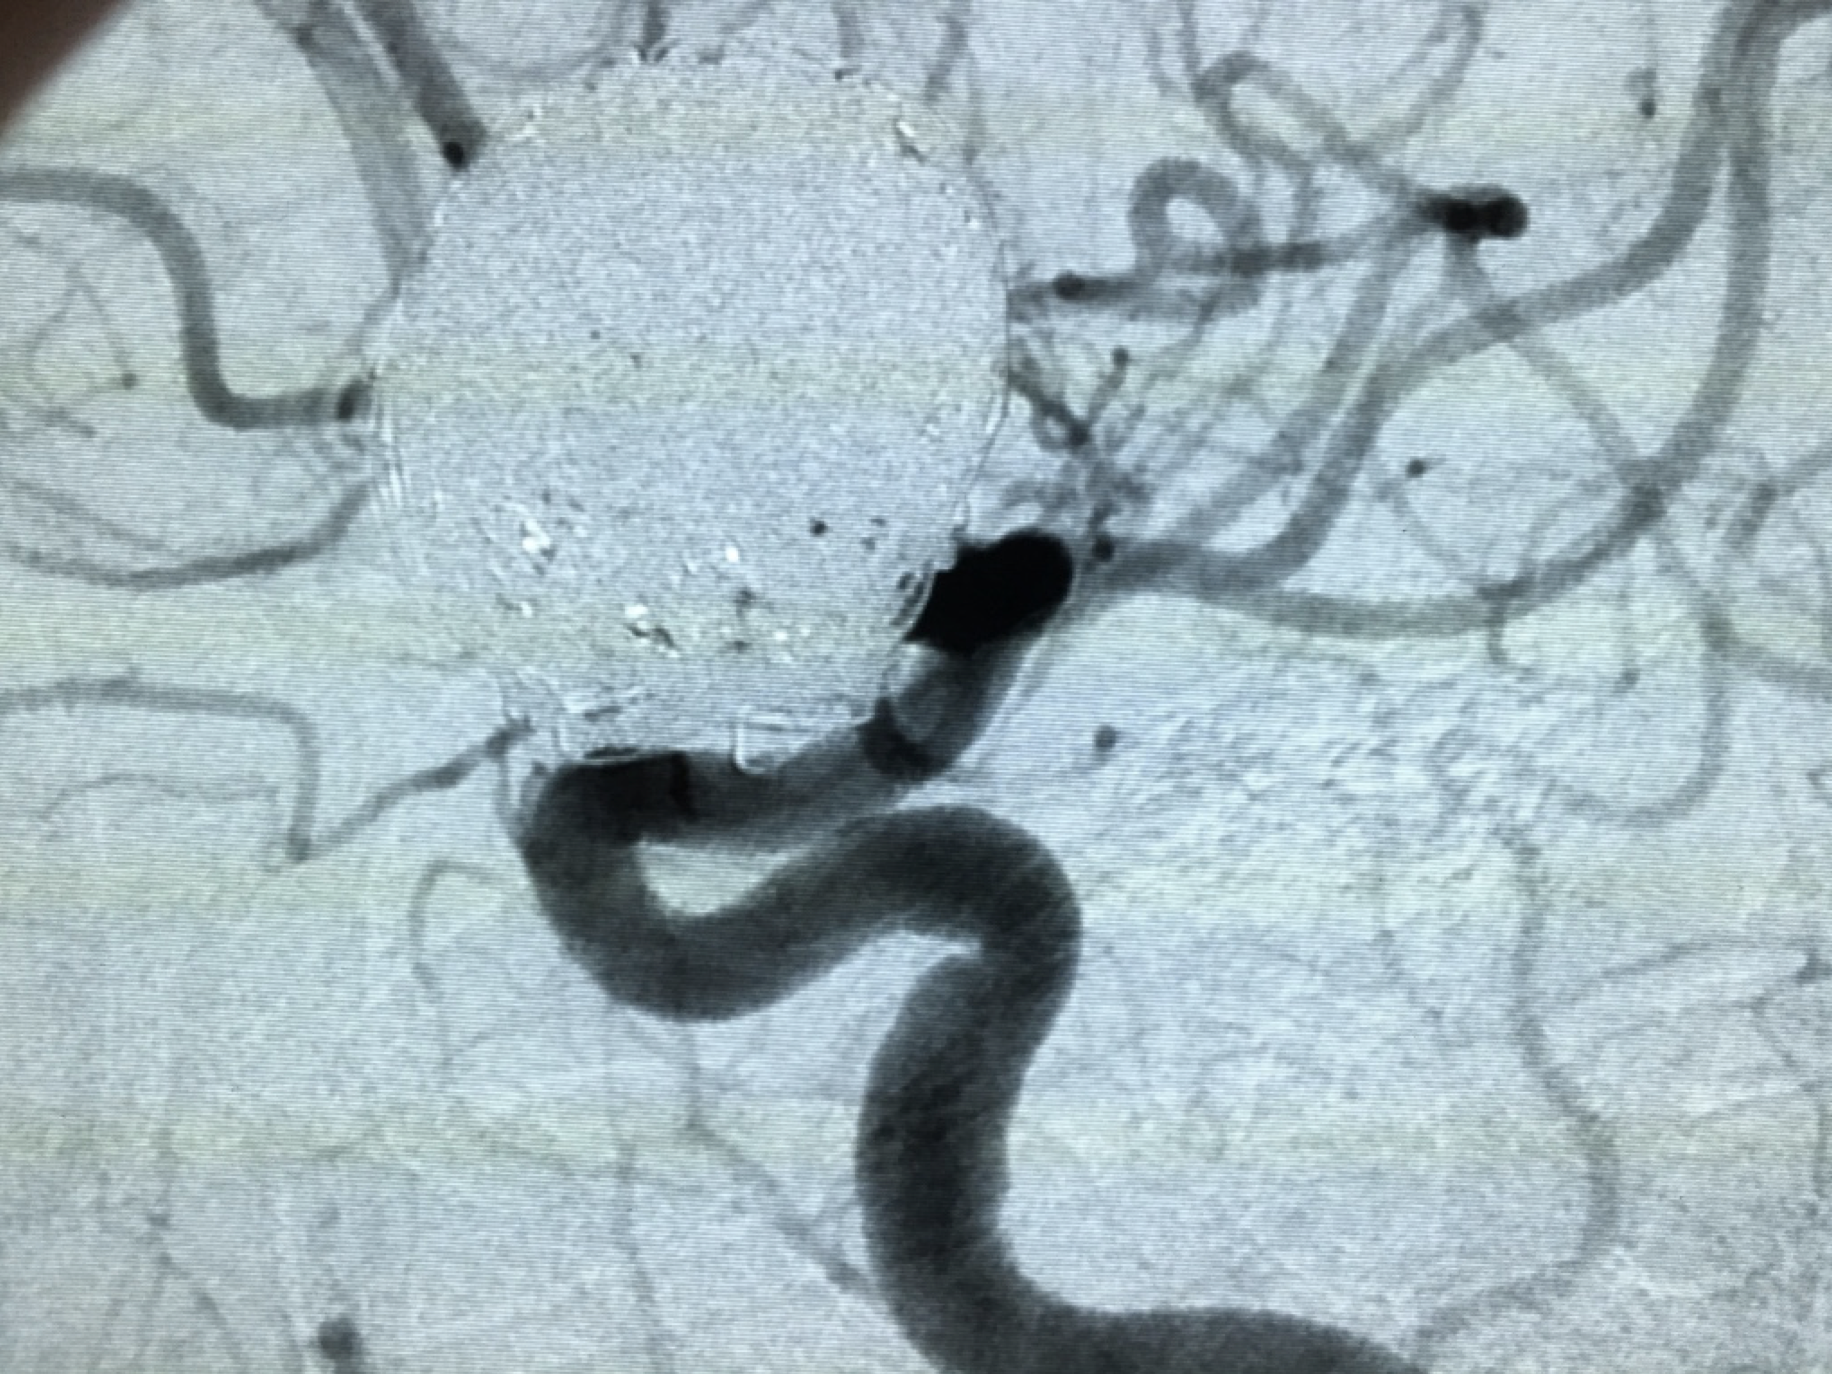

Coil embolization_2